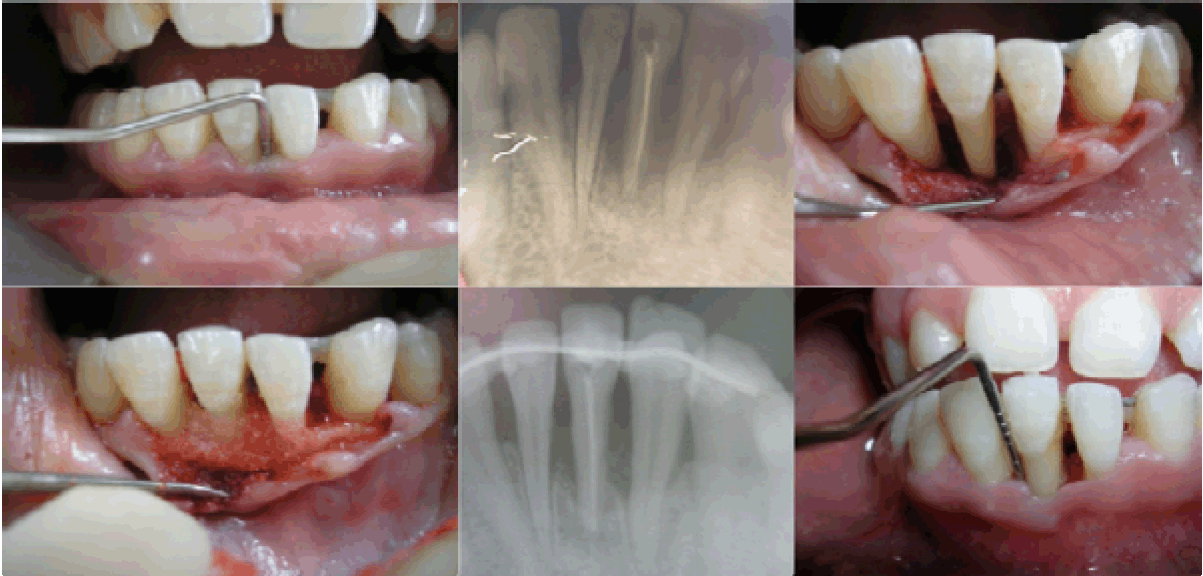

Case 4: A 17-year-old female reported with the chief complaint of pus discharge and mobility in relation to lower anterior tooth since two months. She had first noticed dull ache in the tooth six months back, which subsided after taking medication. Her main concern was loss of tooth. Clinically, there was a deep pocket on both mesial and distal aspects of the tooth # 31. There was bleeding on probing and advanced grade II mobility. Radiograph revealed a significant osseous destruction around 31, 32 and 41. After endodontice therapy I 31, splinting was done to stabilize the tooth and improve healing. After complete debridement a deep intraosseous defect was evident. A bone graft substitute was placed and flap sutured.

In the Case 1, clinical as well as radiographic picture at sixth month showed reduction in pocket depth and osseous lesions in 36, 46 and 27 (Figure 1). In Case 2, at the time of evaluation at ninth month postoperative, there was significant decrease in the radiolucency in 25, 35 as well as reduction in the pocket depth (Figure 2). In Case 3, following root resection, 26 was clinically healthy and a radiograph at sixth month revealed reduction in radiolucency around the roots (Figure 3D). In Case 4 involving tooth #31, the tooth appeared healthy with no pain or pus discharge. Radiograph showed some amount of bone fill.

Cursor on image to zoom/Click text to open image

Figure 4: Case 4 tooth #31.